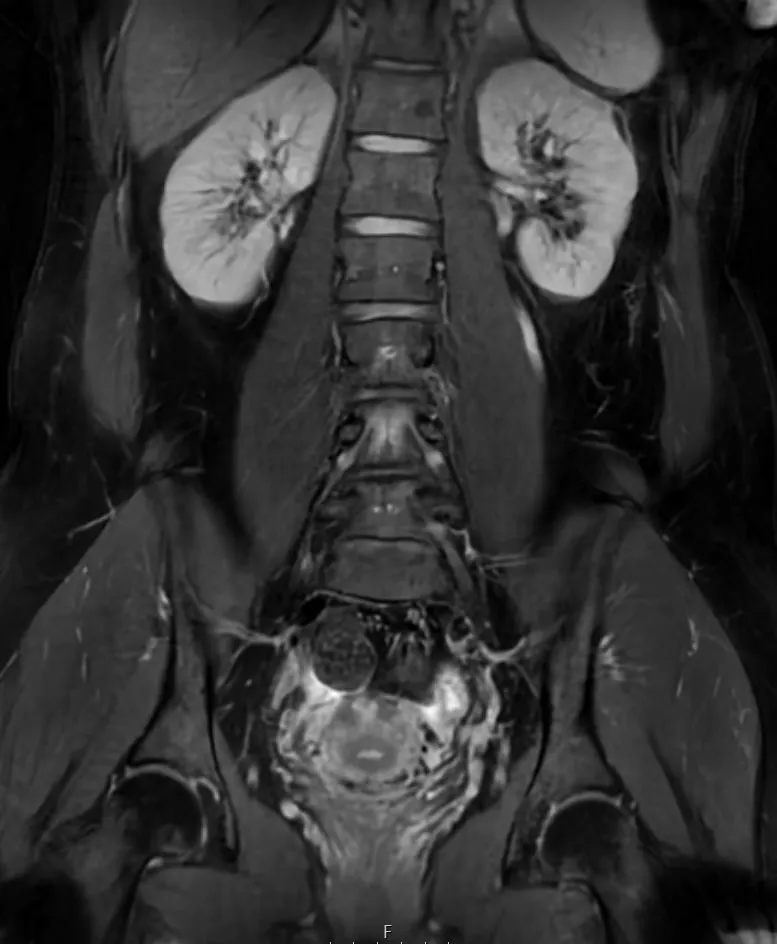

Eksempler på MR Scanninger

En gynækologisk MR-scanning af kvindelige kønsorganer er en skånsom og præcis undersøgelse, der giver detaljerede billeder af underlivet. Vores 3 tesla MR-scanner bruger et magnetfelt og radiobølger til at skabe tydelige billeder af bløddele som livmoder, æggestokke og omkringliggende væv – helt uden brug af røntgenstråling.

Denne type undersøgelse er særligt god til at undersøge og diagnosticere forskellige tilstande i underlivet, der kan være svære at opdage med andre metoder. MR-scanning kan give et klart og detaljeret billede af eventuelle forandringer eller sygdomme i de kvindelige kønsorganer.